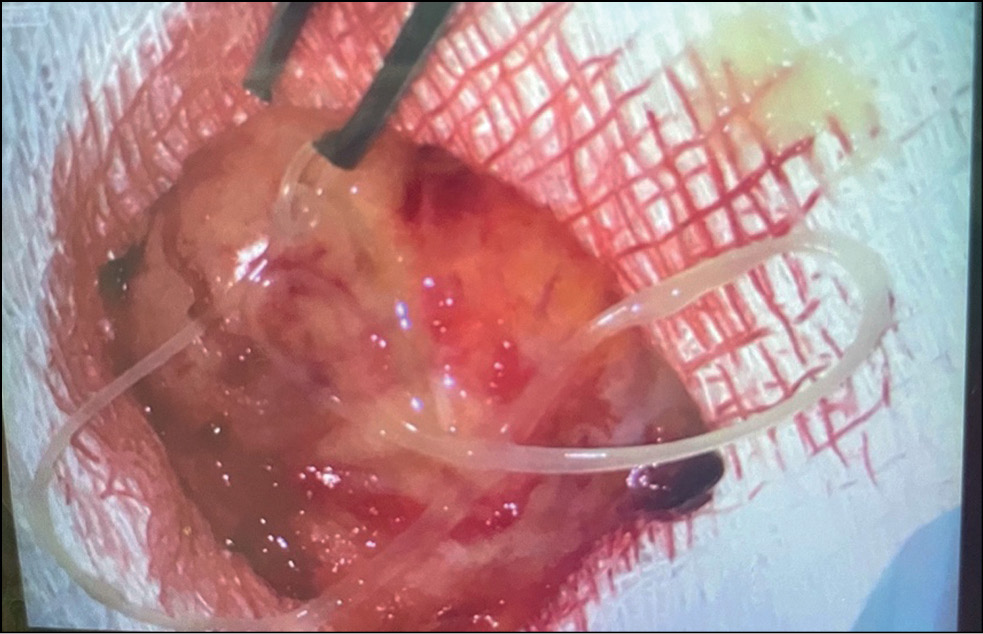

В процессе выполнения хирургического вмешательства под верхней орбитальной стенкой было выявлено плотное образование неправильной округлой формы, интимно спаянное со слёзной железой, верхней прямой мышцей, леватором верхнего века. При вскрытии плотной капсулы скальпелем выделилось слизистое светло-жёлтое отделяемое с включением гельминта — круглого червя. Материал направлен на патогистологическое исследование (рис. 5).

Рис. 5. Плотное образование неправильной округлой формы с слизистым светло-жёлтым отделяемым с включением паразита круглого червя.

Fig. 5. A dense formation of an irregular rounded shape with a light-yellow mucous discharge with the inclusion of a parasite a roundworm.

Согласно данным патогистологического исследования, в операционном материале было обнаружено образование плотной консистенции в виде сформированной тонкостенной капсулы светло-жёлтого цвета. Вокруг капсулы дифференцировали очаг казеозного некроза, окружённого кольцом воспалительной инфильтрации со скоплениями эозинофилов и массивным разрастанием фиброзной ткани. Капсула содержала паразит, имевший вид узкой ленточки размером 12 х 1 х 1 мм, идентифицированный как Dirofilaria repens.